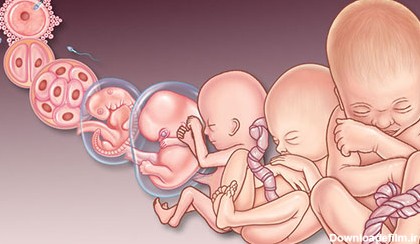

تشکیل جنین در چندین مرحله انجام می شود. والدین و مخصوصاً مادران می خواهند از وضعیت رشد و تکامل فرزند خود در دوران بارداری مطلع شوند. خوشبختانه علم پزشکی سالهاست که این موضوع را برای والدین آسان ساخته و به کمک سونوگرافی والدین می توانند شکل و وضعیت جنین خود را ببینند. مقدمه: هرچند تشکیل …

روند و مراحل رشد جنین در دوران بارداری، ماه به ماه و هفتگی را در این مقاله گهواره بیان میکنیم. عکس مراحل رشد جنین انسان هفته به هفته را مشاهده میکنید.

بارداری هفته به هفته و تغییر وضعیت جنین عکس این دوران را می توان به سه سه ماهه بارداری تقسیم کرد که در هر یک وقایع خاصی اتفاق می افتد؛ سه ماهه اول از...